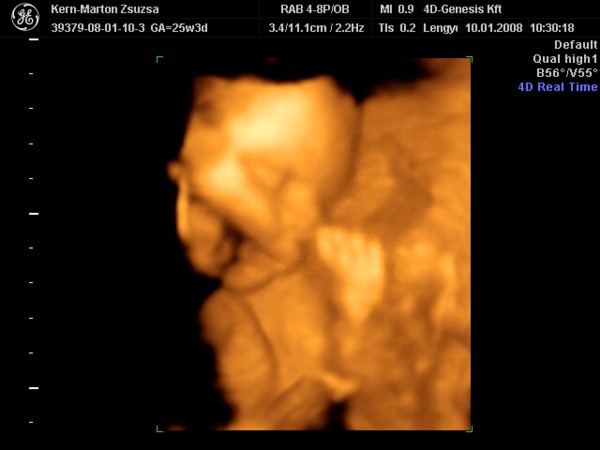

Zsu,tényleg nagyon jól sikerült elkapni az első képen a lánykádat.Azt tudom,hogy kis vöröske Kata,de a 2 kép közül melyik az "igazi" vagy legalábbis melyik hasonlit jobban rá?Tudom,hogy a fényképező rengeteget csal